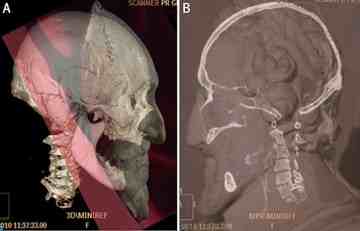

The team could not recover uncontaminated DNA in order to match it to the king's descendants, but the researchers completed a digital facial reconstruction of the skull that matched the plaster mold of Henry IV's face made just after his death.

Researchers, led by forensic medical examiner and osteo-archaeologist Philipp Charlier of University Hospital R Poincaré in Garches, France, compared the head with sculptures and portraits of Henry, who had been assassinated in 1610, and digitally reconstructed the face. The result was a dead ringer for the beloved king.